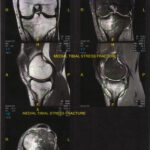

Difference Between Shin Splint and Stress Fracture